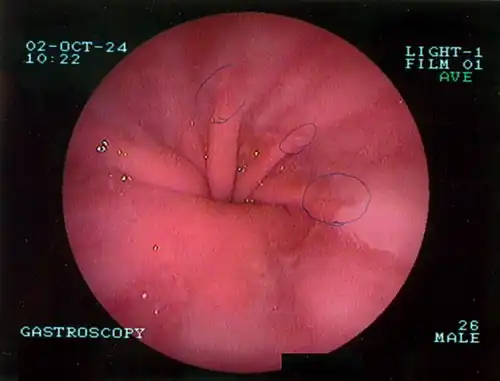

Upper GI endoscopy depicting hiatal hernia -

Upper GI endoscopy in retroflexion showing Type I hiatal hernia -